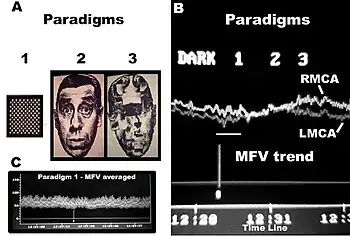

Conventional FTCD has limitations for the study of cerebral lateralization. For example, it may not differentiate the lateralising effects due to stimulus characteristics from those due to light responsiveness, and does not distinguish between flow signals emanating from cortical and subcortical branches of the cerebral arteries of the circle of Willis. Each basal cerebral artery of the circle of Willis gives origin to two different systems of secondary vessels. The shorter of these two is called the ganglionic system, and the vessels belonging to it supply the thalami and corpora striata; the longer is the cortical system, and its vessels ramify in the pia mater and supply the cortex and subjacent brain substance. Furthermore, the cortical branches are divisible into two classes: long and short. The long or medullary arteries pass through the grey substance and penetrate the subjacent white substance to the depth of 3–4 cm. The short vessels are confined to the cortex. Both cortical and ganglionic systems do not communicate at any point in their peripheral distribution, but are entirely independent of each other, having between the parts supplied by the two systems, a borderline of diminished nutritive activity.[18] While, the vessels of the ganglionic system are terminal vessels, the vessels of the cortical arterial system are not so strictly "terminal". Blood flow in these two systems in the middle cerebral artery (MCA) territory supplies 80% of both hemispheres,[19] including most neural substrates implicated in facial processing, language processing and intelligence processing at cortical and subcortical structures. The measurements of mean blood flow velocity (MFV) in the MCA main stem could potentially provide information about downstream changes at cortical and subcortical sites within the MCA territory. Each distal arm of the MCA vascular system could be separated into "near" and "far" distal reflection sites for the cortical and ganglionic (subcortical) systems, respectively. To accomplish this objective, one method is to apply Fourier analysis to the periodic time series of MFV acquired during cognitive stimulations. Fourier analysis would yield peaks representing pulsatile energy from reflection sites at various harmonics, which are multiples of the fundamental frequency.[20][21] McDonald in 1974 showed that the first five harmonics usually contain 90% of the entire pulsatile energy within the system of pressure/flow oscillations in the peripheral circulation. It could be presumed that each arm of the vascular system represents a single viscoelastic tube terminated by impedance, creating a single reflection site.[22] Psychophysiologic stimulation induced vasomotor activity at each terminal site sets up a standing sinusoidal wave oscillation, comprising a summation of waves due to effects of incident, reflected, and re-reflected waves from distal to proximal point of measurement. fTCDS studies are performed with the participant placed in a supine posture with their head up at about 30 degrees. The probe holder headgear (e.g. LAM-RAK, DWL, Sipplingen, Germany) are used with a base support on two earplugs and on the nasal ridge. Two 2-MHz probes are affixed in the probe holder and insonation performed to determine the optimal position for continuous monitoring of both MCA main stems at 50 mm depth from the surface of the probe. A serial recording of MFV for each stimulus is acquired and latter used for Fourier analysis. Fourier transform algorithm uses standard software (for example, Time series and forecasting module, STATISTICA, StatSoft, Inc.). The most efficient standard Fourier algorithm requires that the length of the input series is equal to a power of 2. If this is not the case, additional computations have to be performed. To derive the required time series, the data were averaged in 10-second segments for 1-minute duration or each stimulus, yielding 6 data points for each participant and a total of 48 data points for all eight men and women, respectively. Smoothing the periodogram values was accomplished using a weighted moving average transformation. Hamming window was applied as a smoother.[23][24] The spectral density estimates, derived from single series Fourier analysis, were plotted, and the frequency regions with the highest estimates were marked as peaks. The origins of the peaks are of interest in order to determine the reliability of the present technique. The fundamental (F), cortical (C) or memory (M), and subcortical (S) peaks occurred at regular frequency intervals of 0.125, 0.25, and 0.375, respectively. These frequencies could be converted to Hz, assuming that the fundamental frequency of cardiac oscillation was the mean heart rate. The fundamental frequency (F) of the first harmonic could be determined from the mean heart rate per second. For example, a heart rate of 74 bpm, suggests 74 cycles/60 or 1.23 Hz. In other words, the F-, C-, and S-peaks occurred at multiples of the first harmonic, at second and third harmonics, respectively. The distance of the reflection site for F-peak could be presumed to emanate from a site at D1 = wavelength/4 = cf/4 = 6.15 (m/s)/(4×1.23 Hz) = 125 cm, where c is the assumed wave propagation velocity of the peripheral arterial tree according to McDonald, 1974. Given the vascular tortuosity, the estimated distance approximates that from the measurement site in the MCA main stem, to an imaginary site of summed reflections from the upper extremities, close to the finger tips when stretched sideways.[25] The C-peak occurred at the second harmonic, such that the estimated arterial length (using common carotid c = 5.5 m/s)[26] was given by D2 = wavelength/8 = cf2/8 = 28 cm, and a frequency f of 2.46 Hz. The distance approximates the visible arterial length from the main stem of the MCA, through vascular tortuosity and around the cerebral convexity, to the end vessels at distal cortical sites such as the occipito-temporal junction on carotid angiograms of adults.[25] The S-peak occurred at the third harmonic, and may have arisen from an estimated site at D3= wavelength/16 = cf3/16 = 9.3 cm and a frequency f3 of 3.69 Hz. The latter approximates the visible arterial length of the lenticulostriate vessels from the main stem of the MCA on carotid angiograms.[27] Although not displayed, the fourth harmonic would be expected to arise from the MCA bifurcation in closest proximity to the measurement site in the main stem of the MCA. The pre-bifurcation length from the measurement point would be given by D4 = wavelength/32 = cf4/32 = 3.5 cm and a frequency f4 of 4.92 Hz. The calculated distance approximates that of the segment of MCA main stem just after the carotid bifurcation, where probably the ultrasound sample volume was placed, to the MCA bifurcation. Thus, these estimates approximate actual lengths. However, it has been suggested that the estimated distances may not correlate exactly with known morphometric dimensions of the arterial tree according to Campbell et al., 1989. The method was first described by Philip Njemanze in 2007, and was referred to as functional transcranial Doppler spectroscopy (fTCDS).[25] fTCDS examines spectral density estimates of periodic processes induced during mental tasks, and hence offers a much more comprehensive picture of changes related to effects of a given mental stimulus. The spectral density estimates would be least affected by artefacts that lack periodicity, and filtering would reduce the effect of noise.[28] The changes at the C-peak may show cortical long-term potential (CLTP) or cortical long-term depression (CLTD), which has been proposed to be suggest equivalents of cortical activity during learning[25] and cognitive processes. The flow velocity tracings are monitored during paradigm 1 comprising a checkerboard square as object perception are compared to whole face (paradigm 2) and facial element sorting task (paradigm 3). Fast Fourier transform calculations are used to obtain the spectral density and cross amplitude plots in the left and right middle cerebral arteries. The C-peak also called memory (M-peak) cortical peak could be seen arising during paradigm 3, a facial element sorting task requiring iterative memory recall as a subject constantly spatially fits the puzzle by matching each facial element in paradigm 3 to that stored in memory (Paradigm 2) before proceeding to form the picture of the whole face.